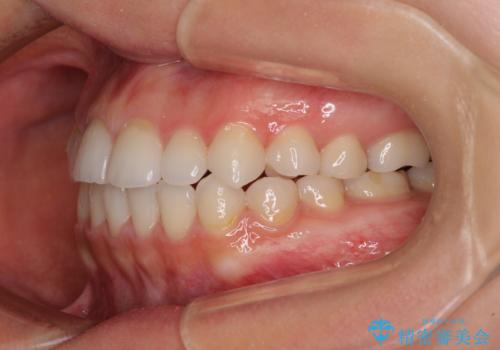

補助装置を事前に使用したことで、あっという間に八重歯が改善し、ハーフリンガルにしては1年半もかからずに治療を終えることができました。